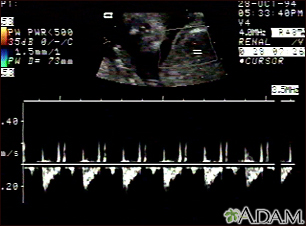

Ultrasound, normal fetus - heartbeatBackUltrasound, normal fetus - heartbeatThis is a normal fetal ultrasound showing one pattern of the fetal heartbeat. Some ultrasound machines have the ability to focus on different areas of the heart and evaluate the heartbeat. This is useful in the early diagnosis of congenital heart abnormalities. E-mail FormEmail ResultsName:Email address:Recipients Name:Recipients address:Message: